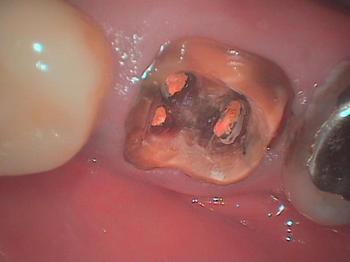

大臼歯に痛みがありメタルコアを除去します

遠心根に破折線らしきものが確認できます。

さらにアップにします

遠心根に破折線が確認できます

メタルコアは歯よりも硬いため楔となって歯を割ってしまいます。

ファイバーコアの選択を考慮すべきです。